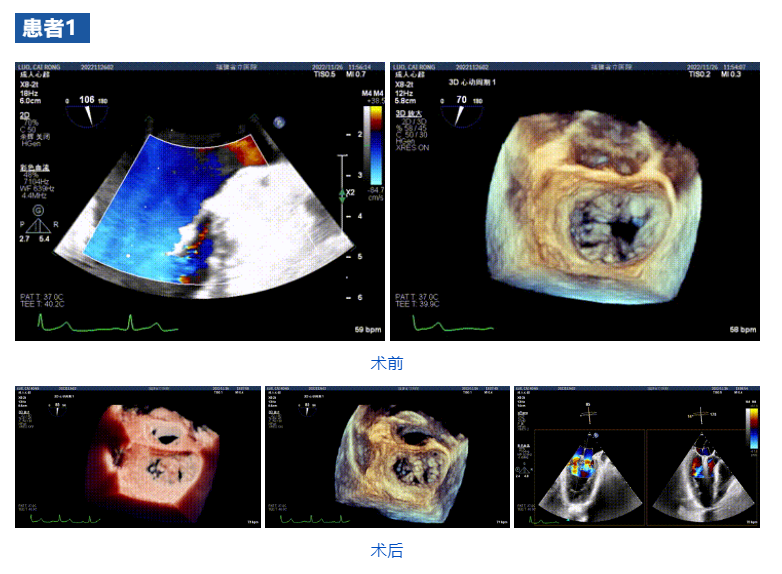

近日,福建省立醫(yī)院心內(nèi)科郭延松教授心臟瓣膜介入治療團(tuán)隊(duì)聯(lián)合浙江大學(xué)醫(yī)學(xué)院附屬第二醫(yī)院王建安教授團(tuán)隊(duì),在福建省首次應(yīng)用JensClip經(jīng)導(dǎo)管瓣膜夾系統(tǒng)為三例二尖瓣重度反流患者開展經(jīng)導(dǎo)管二尖瓣緣對(duì)緣修復(fù)手術(shù)。手術(shù)獲得圓滿成功,患者重獲“心”生。術(shù)后即刻顯示二尖瓣反流顯著改善,術(shù)畢即刻拔管,患者恢復(fù)良好。此次介入手術(shù)的成功再次標(biāo)志著福建省立醫(yī)院心內(nèi)科郭延松教授心臟瓣膜團(tuán)隊(duì)在二尖瓣重度反流修復(fù)介入治療研究領(lǐng)域取得了進(jìn)一步提升,為二尖瓣重度反流患者帶來更多的臨床獲益。

接受治療的三例患者均為器質(zhì)性重度二尖瓣反流(DMR)患者,術(shù)前超聲提示二尖瓣后葉脫垂伴4+反流,左室舒張功能減退。郭延松教授攜同團(tuán)隊(duì)成員陳新敬副教授和洪景宣、方明程、楊清勇主治醫(yī)師、心外科丁杭主任以及超聲科賴寶春、葉振盛主治醫(yī)師共同進(jìn)行病情討論??紤]到患者高齡、基礎(chǔ)疾病多、STS評(píng)分高,為外科手術(shù)極高危患者,不適合進(jìn)行外科開胸二尖瓣手術(shù),因此決定為患者實(shí)施經(jīng)導(dǎo)管緣對(duì)緣修復(fù)介入術(shù)(JensClip經(jīng)導(dǎo)管瓣膜夾系統(tǒng))。

在浙江大學(xué)醫(yī)學(xué)院附屬第二醫(yī)院王建安教授團(tuán)隊(duì)的支持下,手術(shù)經(jīng)股靜脈-房間隔入路,采用全身麻醉插管,在TEE和DSA引導(dǎo)下完成房間隔穿刺。置入JensClip瓣膜夾系統(tǒng)后,在左房調(diào)整瓣膜夾的位置和軸向,后進(jìn)入左室,在TEE引導(dǎo)下捕捉二尖瓣前后瓣葉,并關(guān)閉瓣膜夾。經(jīng)TEE反復(fù)確認(rèn)手術(shù)效果后最終鎖定并釋放瓣膜夾。術(shù)后即刻超聲顯示瓣膜夾位置穩(wěn)定,功能良好,二尖瓣反流由術(shù)前4+減少至微量,手術(shù)圓滿成功。